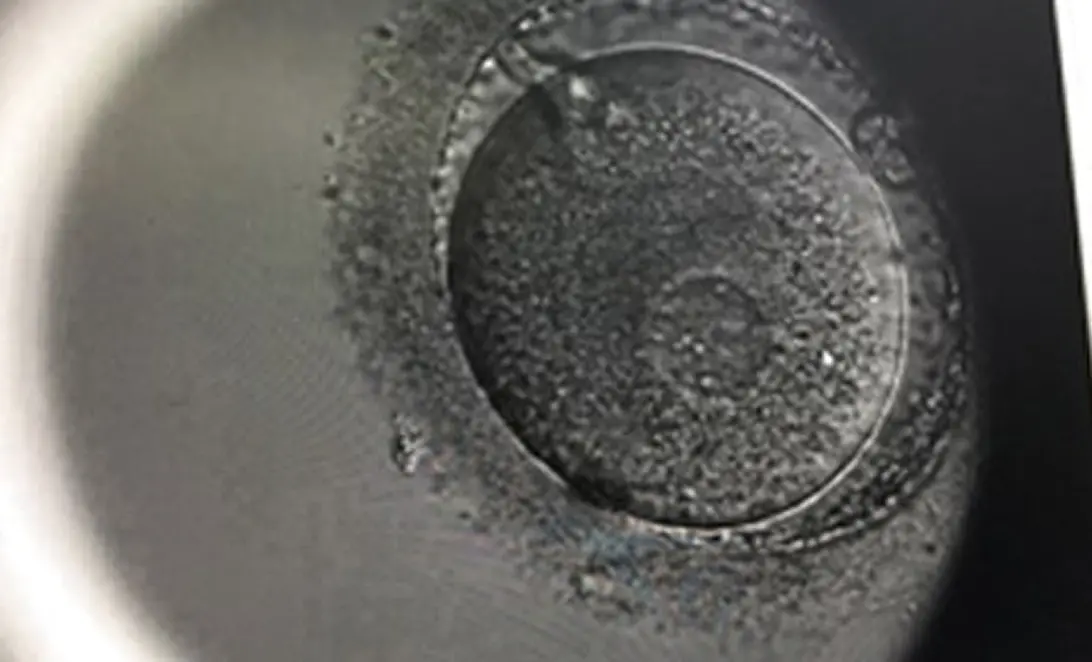

エンブリオスコープとは胚の培養をタイムラプスで録画してより移植に好ましい胚を選別することが出来る、特殊な培養庫の事です。

受精の詳細や胚の分割などを細かく調べられるため、より妊娠しやすい胚を選別することが可能になります。

特に受精や胚発生に関しては、通常の培養庫では観察時間が限られているため詳しい観察が難しい場合もありますが、エンブリオスコープの場合は、連続撮影により容易に判別が出来ます。

当院では、受精から分割までを10分ごとに細かく撮影し、さらに胚を11断面で詳細に観察しています。